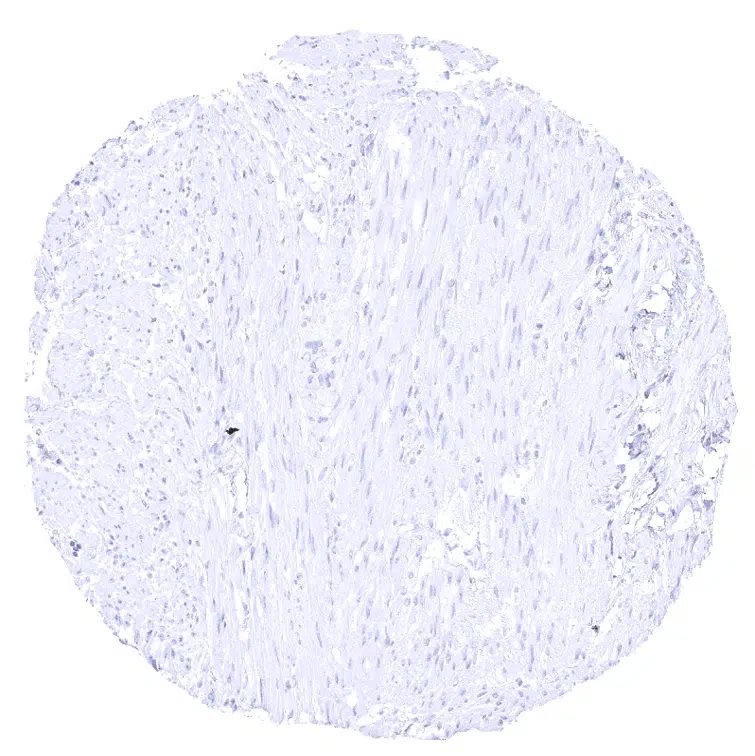

Aorta, Media